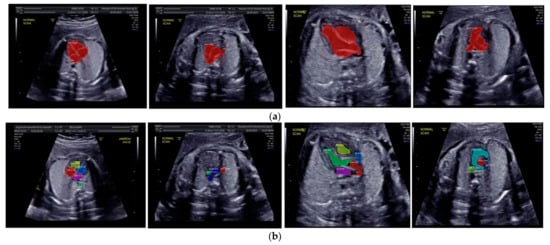

Images with inappropriate anatomical planes (cropped or badly captured) and those with calipers were excluded. The dataset composition was clearly imbalanced (some classes were more frequent than others), as is usually the case in real clinical scenarios. The sample of the raw ultrasound image was based on four views in normal anatomy, as depicted in Figure 2. In such sample, there are the left atrium (LA), left ventricle (LV), right atrium (RA), right ventricle (RV), ductus arteriosus (DUCT), superior vena cava (SVC), aorta ascendens (AoA), aorta descendens (Ao), and main pulmonary artery (MPA), whereas the sample of the raw ultrasound image of abnormal anatomy structure, with the three heart defects such as ASD, VSD, and AVSD condition, is compared to normal anatomy structure in Figure 3. In the abnormal structure, there are hole (H) as heart defect in each condition. Each defect has the variation of hole size; such hole size indicates the disease severity. However, in this study, we only detected the hole, without measuring the hole size.

Figure 2.

Fetal heart scan in four standard views of normal anatomy: (a) 4CH; (b) LVOT; (c) RVOT; and (d) 3VT.

Figure 3.

Fetal heart scan in 4CH view for CHDs detection: (a) ASD; (b) VSD; (c) AVSD; and (d) Normal.